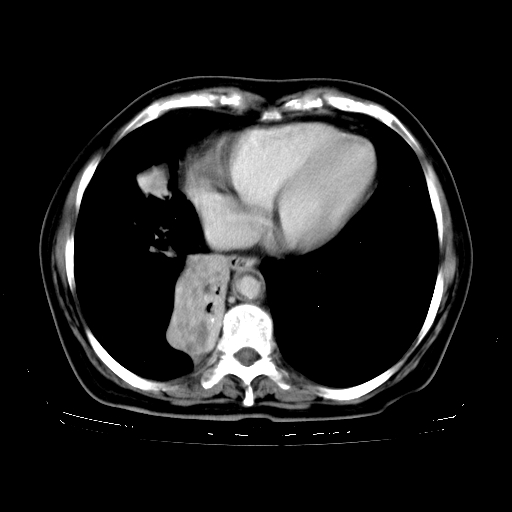

标题: CT23067:女,70岁,咳嗽、咳痰一个月,低热一周。 [打印本页]

女,70岁,咳嗽、咳痰一个月,低热一周。

1.左上肺结核,部分纤维化。右肺中下叶部分肺不张,内见液化、坏死及点状钙化,右中下叶支气管壁增厚、管腔狭窄,见多个点状钙化,结合临床考虑支气管内膜结核,建议痰检查抗酸杆菌并参考血沉。两肺多个小圆点状高密度灶,境界模糊,多考虑结核肺内播散。但本人年龄较大首先应支气管镜检以除外右肺癌。

2.胸主动脉夹层。

一元论:内膜结核伴下肺阻塞性肺炎并双肺播散!另:主动脉夹层。右侧少量胸腔积液。

继发型肺结核,右下肺支气管内膜结核.右侧少量胸腔积液.主动脉夹层.

支气管内膜结核肺内播散.右侧少量胸腔积液.主动脉夹层.